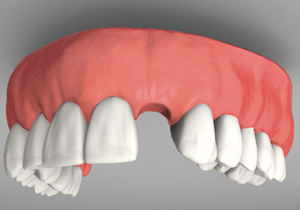

A Upper Implant Frame To Support A Denture